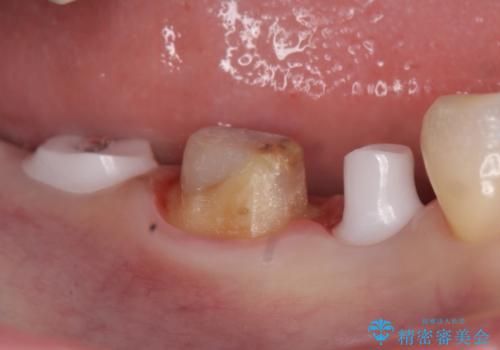

- 右下の奥歯の被せ物が外れてしまったので診て欲しいといらっしゃった方の症例です。

右下7は欠損しており、右下5は保存不可能だったため、インプラントによる欠損補綴を行いました。

インプラント埋入時には骨が不十分な部位に骨増生を行っております。